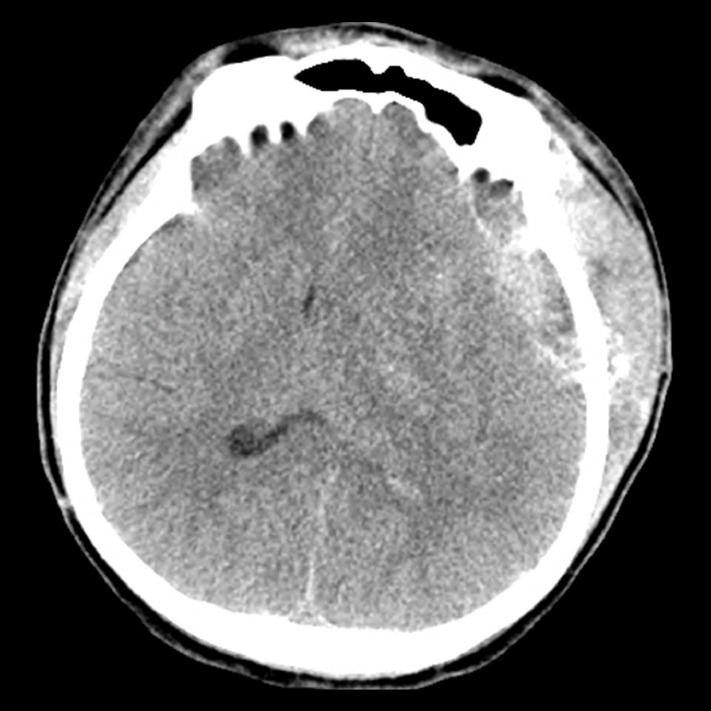

Objective: We evaluated the role of subgaleal closed suction drains in postoperative epidural hematoma (EDH) and wound complications following pterional craniotomy for cerebral aneurysm.

Methods: We reviewed 5,280 pterional craniotomies performed on 5,139 patients between January 2006 and December 2020. A drain was placed subgalealy and tip of drain was positioned between the bone flap and the deep temporalis. 1,637 cases (31%) had a subgaleal suction drain. We analyzed demographic and clinical variables related to EDH requiring evacuation and wound complications in patients with and without drains. Univariate and multivariate logistic regression analyses were performed to determine the associated risk factors.

Results: Fourteen cases (0.27%) of EDH requiring evacuation and 30 cases (0.57%) of wound complications were identified. Univariate analysis found that drain insertion, subarachnoid hemorrhage (SAH), and operation time were associated with EDH, while drain insertion, SAH, male gender, older age, and longer operation time were associated with wound complications. Multivariate analysis found no significant association between drain use and EDH (OR=1.62, p=0.402) or wound complications (OR=1.45, p=0.342).

Conclusions: Routine use of subgaleal closed suction drains may not be necessary after pterional craniotomy, as drain insertion was not associated with a reduced risk of EDH requiring evacuation or wound complications.